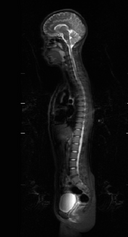

A Full Body MRI uses powerful magnetic fields and radio waves to create detailed images of your body from the head to the waist. It focuses on key areas like:

Brain and blood vessels (MRA of the brain)

Spine (cervical, thoracic, lumbar)